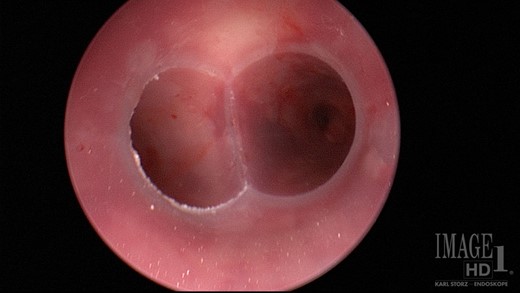

Ten days after the ACell® matrix placement, a rigid bronchoscope was again performed. Complete resolution of the defect had occurred. The Y-stent and the esophageal stent were removed the following week with resolution of symptoms. Repeat imaging following removal of the stents, including a non-contrast CT of the chest and a CT esophagram, demonstrated resolution of the fistulous communication. Repeat bronchoscopy was performed 10 months after stent removal with no evidence of fistula recurrence and minimal persistent inflammation (Fig. 6).